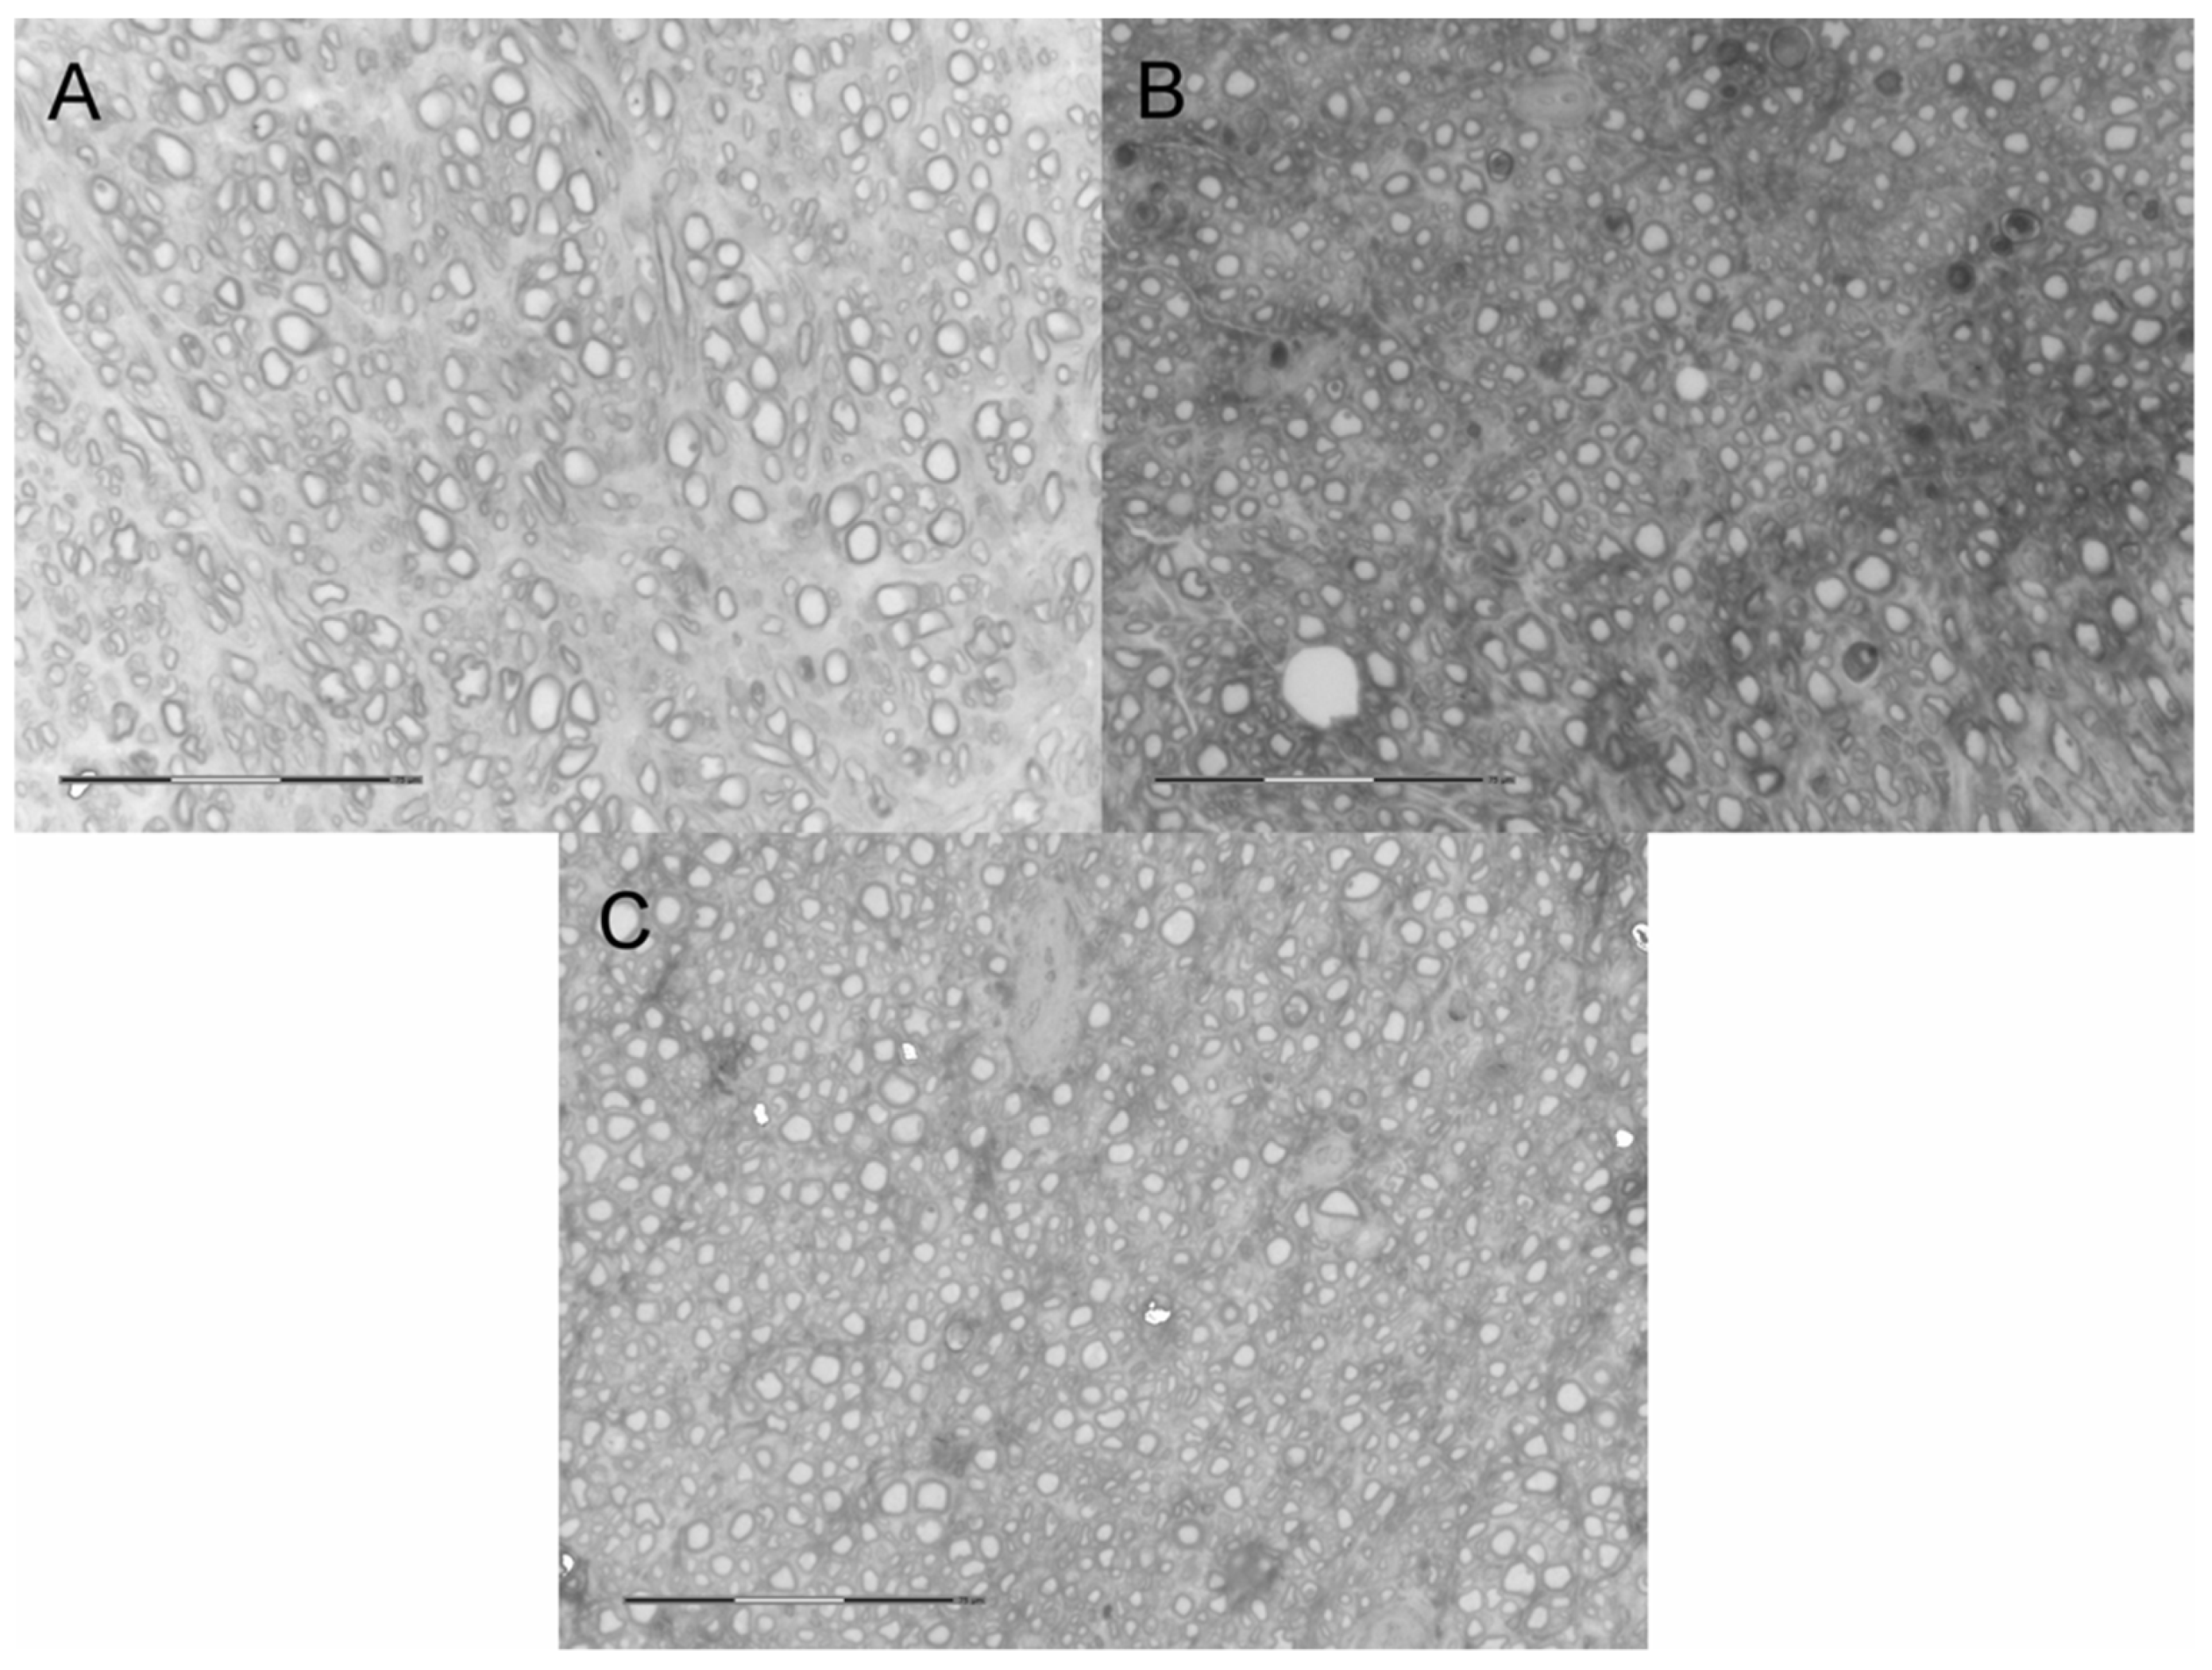

2.5. Neural Tissue